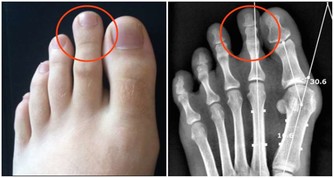

當人出現腳氣、四肢浮腫、消化不良、血壓下降等症狀時,很有可能缺少維生素B1。

維生素B1對於上述的情況有預防作用,需及時補充。